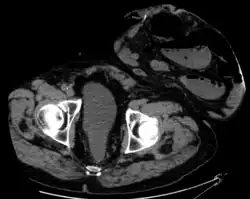

Parastomal hernia is the most common late complication of stomata through the abdominal wall, occurring in 10 to 25% of the patients.[1]